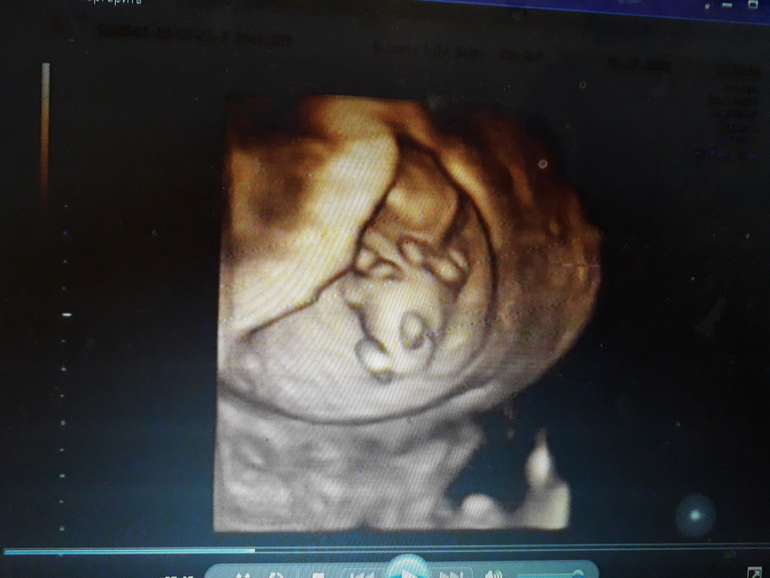

У нас вот такая же проблема...на двух УЗИ была, на первом девочку пообещали...а на втором в 13 недель врач сказал мальчик. А мне так доченьку хочется ( уже 2 сына) вот наше фото с первого скрининга